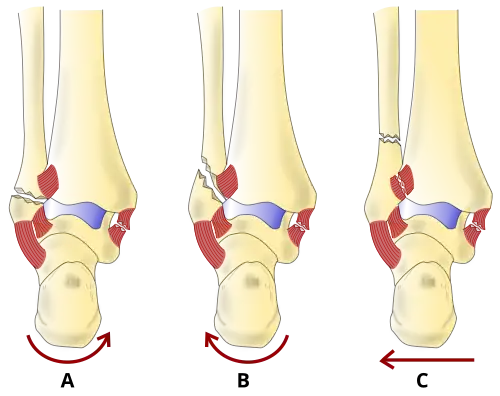

Danis–Weber classification of ankle fractures (Types A, B and C)

The Danis–Weber classification (often known just as the Weber classification) is a method of describing ankle fractures. It has three categories:[1]

Type A

Fracture of the fibula distal to the syndesmosis (the connection between the distal ends of the tibia and fibula). Typical features:

• below level of the ankle joint

• tibiofibular syndesmosis intact

• deltoid ligament intact

• medial malleolus occasionally fractured

• usually stable: occasionally nonetheless requires an open reduction and internal fixation (ORIF) particularly if medial malleolus fractured

Type B

Fracture of the fibula at the level of the syndesmosis. Typical features:

• at the level of the ankle joint, extending superiorly and laterally up the fibula

• tibiofibular syndesmosis intact or only partially torn, but no widening of the distal tibiofibular articulation

• medial malleolus may be fractured or deltoid ligament may be torn

• variable stability

Type C

Fracture of the fibula proximal to the syndesmosis. Typical features:

• above the level of the ankle joint

• tibiofibular syndesmosis disrupted with widening of the distal tibiofibular articulation

• medial malleolus fracture or deltoid ligament injury present

• unstable: requires ORIF

Categories B and C imply a degree of damage to the syndesmosis itself (which cannot be directly visualised on X-ray). They are inherently unstable and are more likely to require operative repair to achieve a good outcome. Type A fractures are usually stable and can be managed with simple measures, such as a plaster of paris cast.